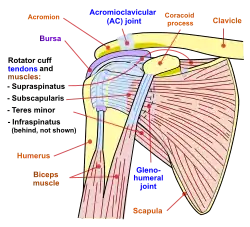

Diagram of the human shoulder joint, front view

Diagram of the human shoulder joint, front view -